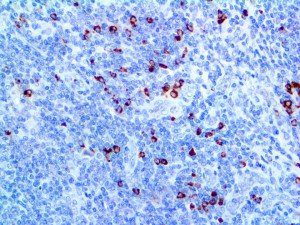

It is the ICU physician who is most likely to witness one of the deadliest manifestations of the abnormal immunological response, the cytokine storm syndrome (CSS). This response is also referred to by some as the cytokine release syndrome (CRS). CSS is characterized by continuous activation and expansion of macrophage and lymphocyte populations, which secrete large amounts of cytokines, causing the cytokine storm. This massive cytokine release is akin to hemophagocytic lymphohistiocytosis (HLH) disease, a syndrome characterized by initial unchecked and persistent activation of cytotoxic T lymphocytes and NK cells.

Clinical and laboratory manifestations of HLH include fever, enlarged liver and/or spleen, neurologic dysfunction, coagulopathy, liver dysfunction, cytopenias (i.e., low levels of erythrocytes, leukocytes, and/or platelets), hypertriglyceridemia, hyperferritinemia, hemophagocytosis, and eventually diminished NK cell activity as the immune system becomes progressively paralyzed. HLH can be familial (primary HLH) or secondary to another disease process (sHLH), such as rheumatic disease, in which it is referred to as macrophage activation syndrome (MAS, characterized by elevated ferritin).